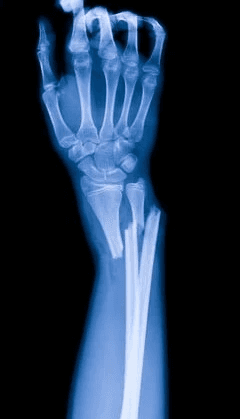

Baleseti sebészet